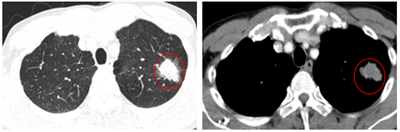

Ung thư phổi là một trong những ung thư có tỷ lệ mắc và tử vong cao nhất trên toàn thế giới. Theo GLOBOCAN 2022, ung thư phổi đứng thứ hai về số ca mắc mới với khoảng 2,5 triệu trường hợp mỗi năm và...